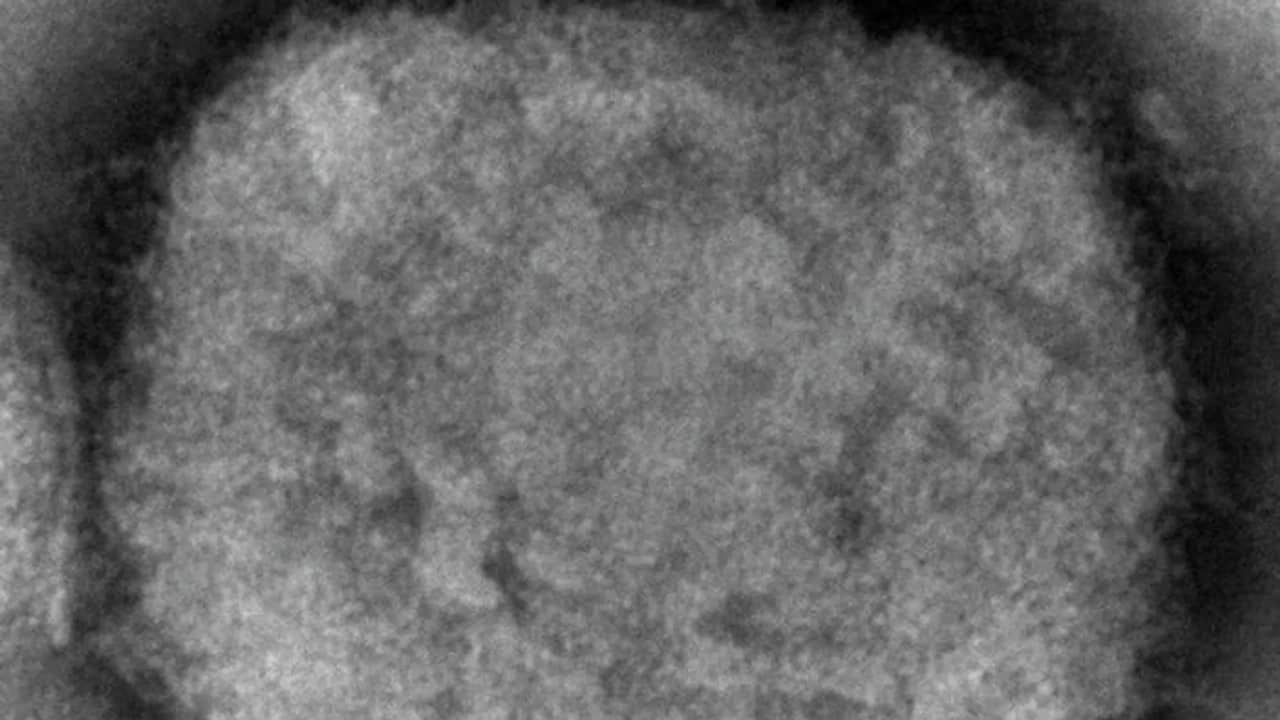

İspaniyanın səhiyyə naziri Karolina Darias Avropa Birliyinə (Aİ) üzv olan 27 ölkənin meymun çiçəyi (meymun çiçəyi) xəstəliyinə qarşı peyvənd və antiviral dərmanlar almağa qərar verdiyini açıqlayıb.

7NEWS.az xəbər verir ki, Danimarka "Bavariya Nordic” şirkəti tərəfindən istehsal edilən və Avropa Dərman Agentliyi tərəfindən təsdiq edilmiş "Ankara ştammı" adlı çiçək peyvəndi variantının Aİ-də meymun çiçəyi vaksinlərində istifadə üçün alınacağını açıqladı.